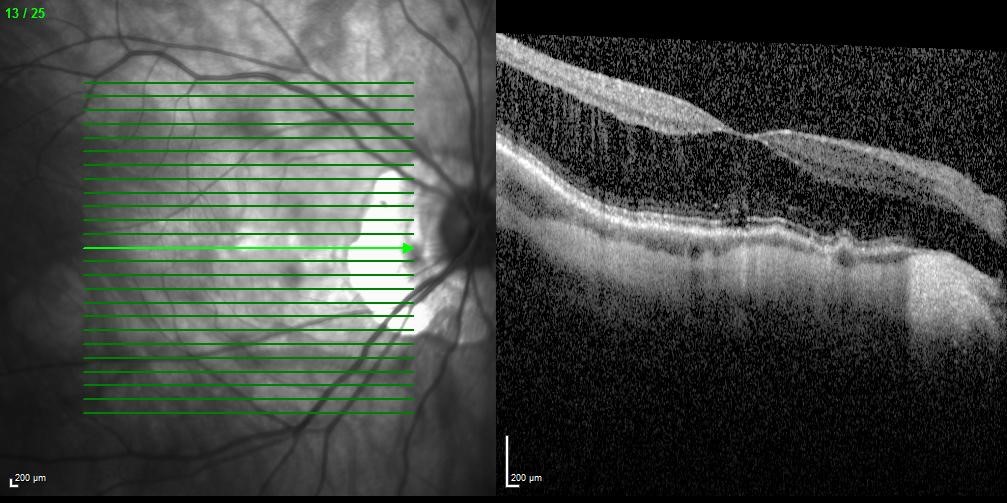

Trial-fitting with the Eyespace Scleral lens was carried out with the aid of anterior OCT to assess central clearance and landing zone alignment. Despite his large corneal diameter (HVID) the lens size of 16.5mm was chosen as the larger 17.5mm size decentered inferiorly following insertion. This also matched the size of the KATT lens he has used in the past. I always assess flexure of the lens with over-topography during trial fitting as this gives me an idea of the level of scleral toricity. The Scleral Shape Study from Pacific University showed us that the majority of sclera are asymmetrical and tend to be flatter in the nasal aspect. Fitting a spherical scleral lens to an asymmetrical sclera often results in lens flexure, leading to residual astigmatism. In moderate-severe cases it can also cause the lens to be unstable on the eye.

Anterior OCT of the lens showing 160µm of central clearance and well-aligned base curve

OCT of the inferior scleral landing zone showing limbal clearance and well-aligned landing angle

Using the data from the trial fitting process the patient’s first custom lens was designed with 200µm of sagittal difference between meridians and a spherical base curve and power of 7.8mm and -3.50D respectively. On delivery the lens had even scleral alignment and after settling 160µm of central clearance. The lens was quick to align with the ‘flat’ meridian’s marking along 30 degrees, matching the principal meridians of flexure on the over-topography of the trial lens.